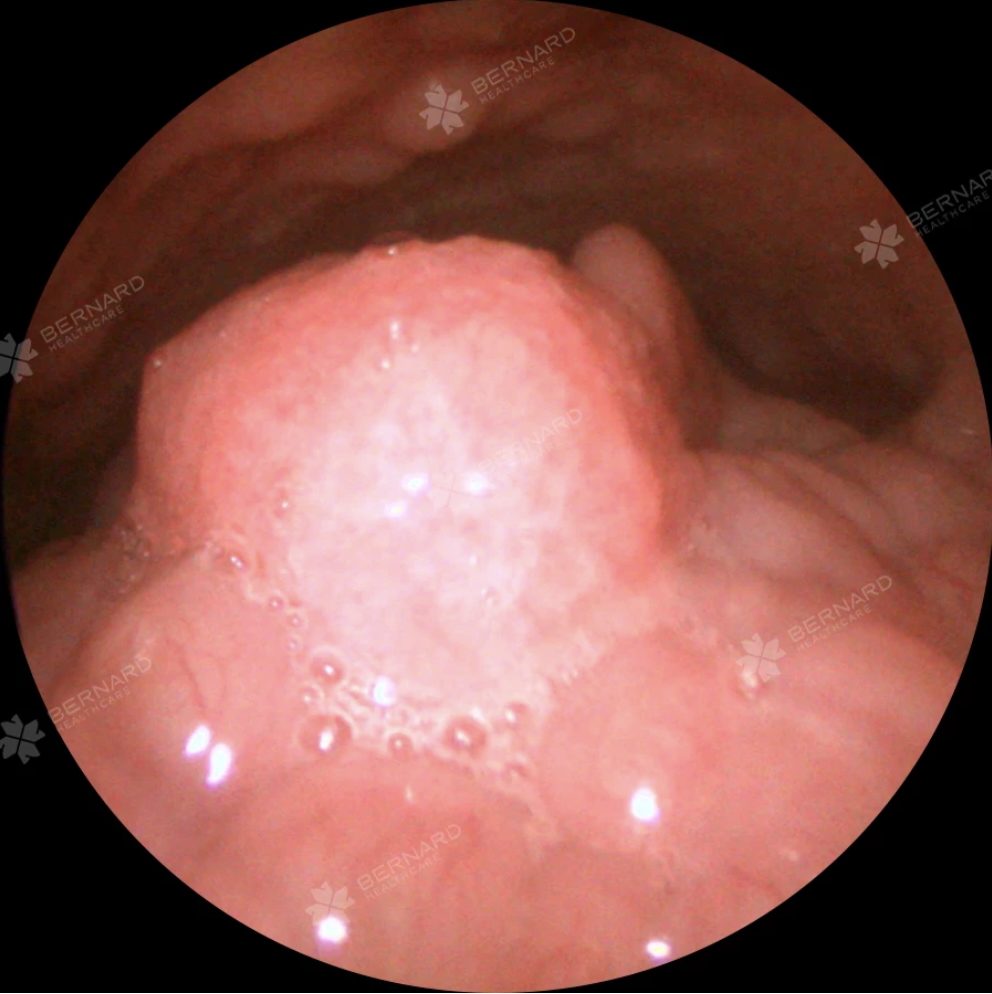

Mọi hạng mục kiểm tra ban đầu đều bình thường cho đến khi bác sĩ tiến hành nội soi Tai Mũi Họng. Tại khu vực hạ họng - thanh quản, cụ thể là vị trí nắp thanh môn bên phải, bác sĩ phát hiện một khối u nhú nhỏ nằm ở vùng thanh nhiệt - xoang lê, trong khi niêm mạc vòm họng hoàn toàn sạch sẽ.